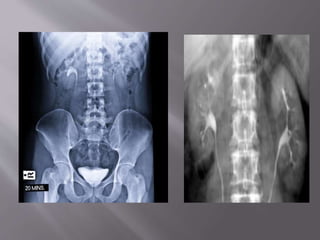

 An Intravenous Pyelogram (IVP) is an x-ray

examination of the kidneys, ureters, and

urinary bladder.

 An IVP study uses a contrast material to

enhance urinary structures in x-ray images.

 The iodine contrast material is injected into

the patient's venous system, and its progress

through the urinary tract is then recorded on a

series of quickly captured images.

 Show the anatomy & function of the kidneys